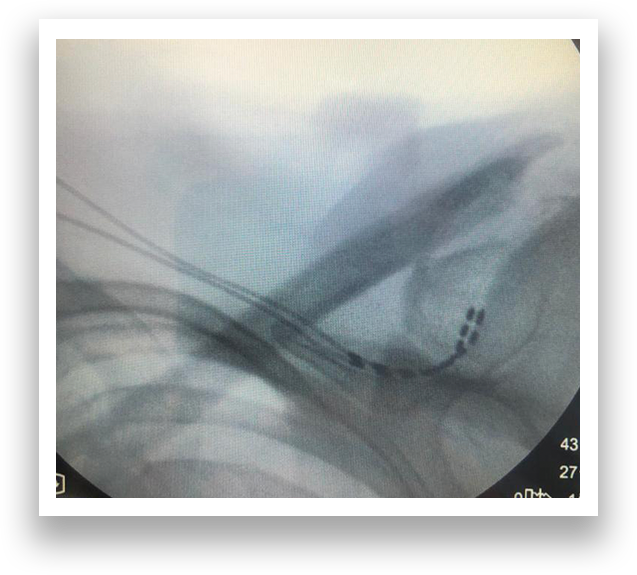

X-ray/MRI scan overlay